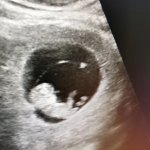

输卵管,女性重要的孕育生殖器之一,担负着运送精子、捡拾卵子及将受精卵运送到宫腔的重要使命。只有输卵管畅通无阻,女性才能受孕产子,使生命延续。然而,临床上却有不少女性因输卵管疾病而无法顺利怀孕。

医生指出,输卵管的微环境评估——高端的诊疗标准是在普通造影之上的,沈阳京科医院采用自动数字化DR输卵管高精造影(SG):清楚的显示输卵管是否通畅、准确抓取堵塞部位、清晰观察子宫内腔形态,以及了解输卵管的走形、大小、狭窄部、伞端与盆腔情况。该技术在针对输卵管不孕的检查问题上,准确性更高,为后续的治疗提供了准确的诊断依据。